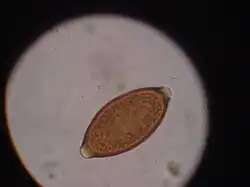

Egg of T. vulpis

Trichuris vulpis is a whipworm that lives in the large intestine of canines in its adult stages. Out of different types of worms, Trichuris vulpis is one of the smaller worms with a size ranging from 30–50 mm in length. As the name suggests, the worm has a whip-like shape with distinct features including a small, narrow anterior head, which is the digestive part of the worm, and a larger posterior tail, which is the reproductive part of the worm. Eggs from T. vulpis are oval shaped with bipolar plugs and contain a thick outer shell. Their sizes range from 72–90 μm in length and 32–40 μm in width.[1] Because of their thick outer shell, T. vulpis eggs are very resistant to environmental extremes such as freezing or hot temperatures, thus allowing for their long viability in the outside world.[2]

Infection of this parasite can be confirmed with detection of eggs in the canine's feces. Adult T. vulpis females can produce more than 2,000 eggs per day. These eggs can be detected in the canine's feces by the fecal flotation method.[14] This method utilizes the differences of specific gravity of eggs, fecal debris, and the flotation solution.[15] Although these eggs are dense, the use of proper fecal flotation technique using a sugar solution and centrifugation can increase the chances of identifying these eggs in a fecal sample.[16] Multiple fecal samples may need to be tested as the eggs may be shed periodically.[17]